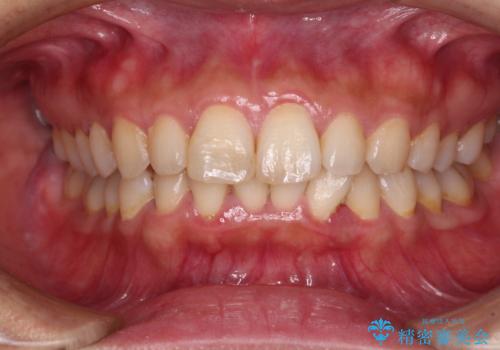

転んで欠けてしまった前歯 オーダーメイドのオールセラミッククラウン

- 転んで欠けてしまった前歯を気にして来院された患者様です。

転んだ際に歯の先端1/4ほどが欠けてしまい、近医にて修復をしてもらったとのことですが、将来的にオールセラミッククラウンを装着する可能性を説明されたため、当院にて補綴治療を行うこととしました。

- 治療費の目安: 15万円(税込)費用は治療当時の料金となります